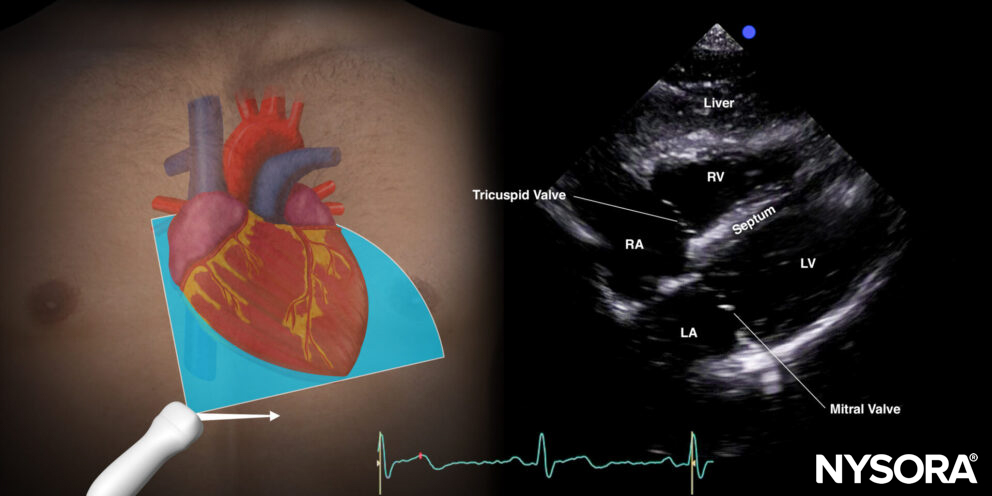

- The subcostal four-chamber view is excellent to rule out tamponade. In the presence of a tamponade, the heart is surrounded by an anechoic layer. More info on tamponade can be found in the cardiac category.

Subcostal four-chamber view.

Reverse Ultrasound Anatomy of the subcostal four-chamber view.